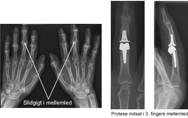

Slidgigt i fingrene er meget almindeligt. Oftest er det tommelens rodled, der påvirkes, men også fingrenes yderled og mellemled kan rammes. Generne kan afhjælpes med en stivgørende operation eller en ledprotese.

Behandlingsmulighederne er flere, og man må i høj grad tilpasse behandlingsplanen til den enkelte person. Nogle led kan stivgøres uden, at håndens funktion nedsættes væsentligt. I andre led er bevægeligheden vigtig for funktionen, hvorfor operation med indsættelse af ledprotese kan komme på tale. Når man planlægger behandlingen, er det også vigtigt at tage højde for personens køn, alder og erhverv.